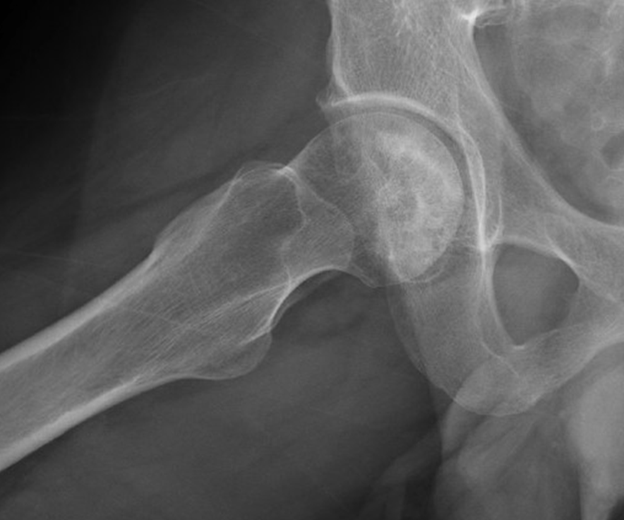

This is another example of avascular necrosis in a patient who was complaining of months of hip pain worsening over the week prior to presentation. The patient had previously undergone a total hip replacement due to AVN of the left hip!

This image of stage 2 AVN has a mixed picture of osteopenia and sclerosis with subchondral cystic changes.